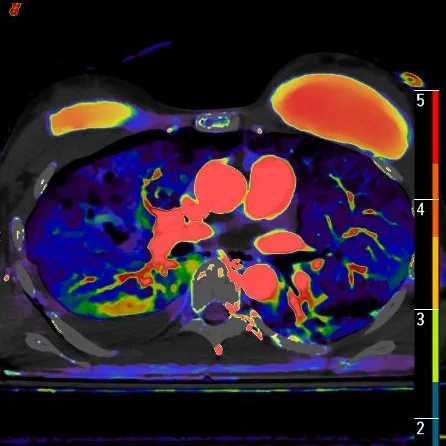

Fusion image nicely demonstrates the perfusion alterations.

Iodine map shows increased perfusion surrounding the lung lacerations. There is also increased perfusion in the area of lung contusion compared to contralateral lung.

On spectral analysis, the central pneumatocele portion of the lung lacerations shows no perfusion, as expected. interestingly, there is increased perfusion around the pneumatocele, and increased perfusion in the contused lung compared to the contralateral left lung anteriorly.

While I am not sure regarding explanation of this "luxury" perfusion, I feel it is most likely related to capillary injury and increased permeability. If this is true, this might account for the penomenon of rapid worsening of infiltrates in case of lung injury.